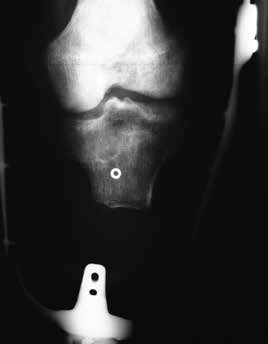

Der kurze Stumpf (proximales Drittel) bedeutet im Knochen mehr Spongiosa. Das wiederum bedeutet wegen der besseren Lastverteilung eine höhere Stumpfendbelastbarkeit um 80 bis 90 %. Höhere Stumpfendbelastbarkeit bedingt mehr Propriozeption. Somit wird der Verlust besserer Biomechanik gegenüber dem mittellangen Stumpf teilweise ausgeglichen. Die Rehabilitation gestaltet sich in der Regel unkompliziert. Die Entfernung der Fibula ist kein Nachteil für die prothetische Versorgung, da der Stumpf eine Dreiecksform besitzt. Im Gegenteil, das Fibulaköpfchen wird nicht prominent, was die Kurzstumpfversorgung erleichtert.

Im Folgenden werden anhand von Fotos aus dem Archiv des Verfassers einige einschlägige Fälle vorgestellt, um häufig vorkommende Fehler aufzuzeigen (Abb. 1–10).